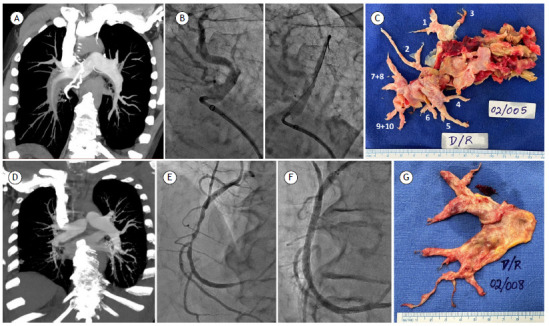

Multimodal treatment of chronic thromboembolic pulmonary hypertension: initial experience at a university hospital in southern Brazil.

慢性血栓栓塞性肺动脉高压的多模式治疗:巴西南部一所大学医院的初步经验。